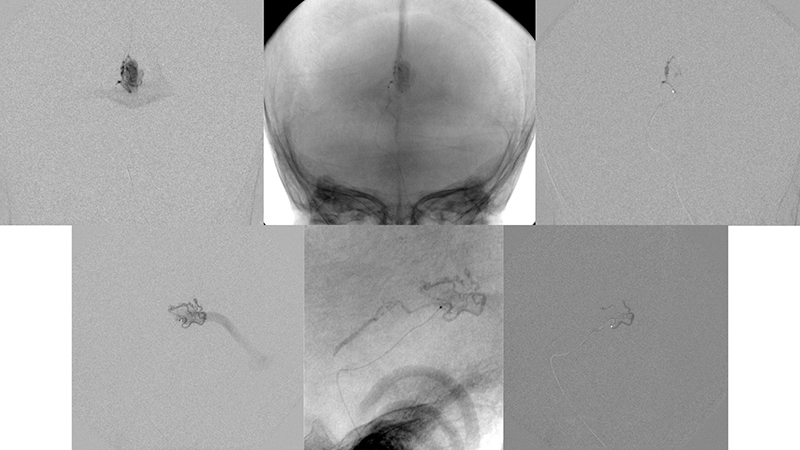

- Προσθιοπίσθια λήψη κατά την έγχυση στην δεξιά έσω καρωτίδα. Η αρτηριοφλεβώδης επικοινωνία της φλέβας του Γαληνού σκιαγραφείται από παλινδρόμηση στην δεξιά υποκλείδιο και σπονδυλική αρτηρία. Η φλεβική παροχέτευση του δεξιού εγκεφαλικού ημισφαιρίου γίνεται πολύ καθυστερημένα, λόγω απόφραξης των εγκαρσίων κόλπων αμφοτερόπλευρα (μαύρα βέλη).

- Πλαγία λήψη κατά την έγχυση στην δεξιά έσω καρωτίδα. Υπάρχει εξεσημασμένη φλεβική συμφόρηση του άνω οβελιαίου κόλπου, προς το σύστημα της φλέβας του Troland (μπλέ βέλος), τον σηραγγώδη κόλπο και τό έδαφος του προσθίου κρανιακού βόθρου (μαύρα βέλη) και το πτερυγοειδές πλέγμα.

- Προσθιοπίσθια λήψη κατά την έγχυση στην αριστερή έσω καρωτίδα. Η αρτηριοφλεβώδης επικοινωνία της φλέβας του Γαληνού σκιαγραφείται από την οπίσθια αναστομωτική αρτηρία. Η φλεβική παροχέτευση του αριστερού εγκεφαλικού ημισφαιρίου γίνεται πολύ καθυστερημένα, λόγω απόφραξης των εγκαρσίων κόλπων αμφοτερόπλευρα (μαύρα βέλη).

- Πλαγία λήψη κατά την έγχυση στην αριστερή έσω καρωτίδα. Η φλεβική παροχέτευση της αρτηριοφλεβώδους επικοινωνίας προς το σύστημα του άνω οβελιαίου κόλπου (κόκκινα βέλη) με εξεσημασμένη φλεβική συμφόρηση και κινητοποίηση παράπλευρων διαμυελικών φλεβών προς το σύστημα της επιπολής μέσης εγκεφαλικής φλεβός (μπλέ βέλος) και διά του σφηνοβρεγματικού κόλπου προς τον σηραγγώδη κόλπο ενώ το εν τω βάθει φλεβικό δίκτυο αποχετεύεται μέσω των αναστομώσεων με το σύστημα της εν τω βάθει μέσης εγκεφαλικής φλεβός (διακεκομμένο μπλέ βέλος) προς το σύστημα επίσης του σηραγγώδους κόλπου.